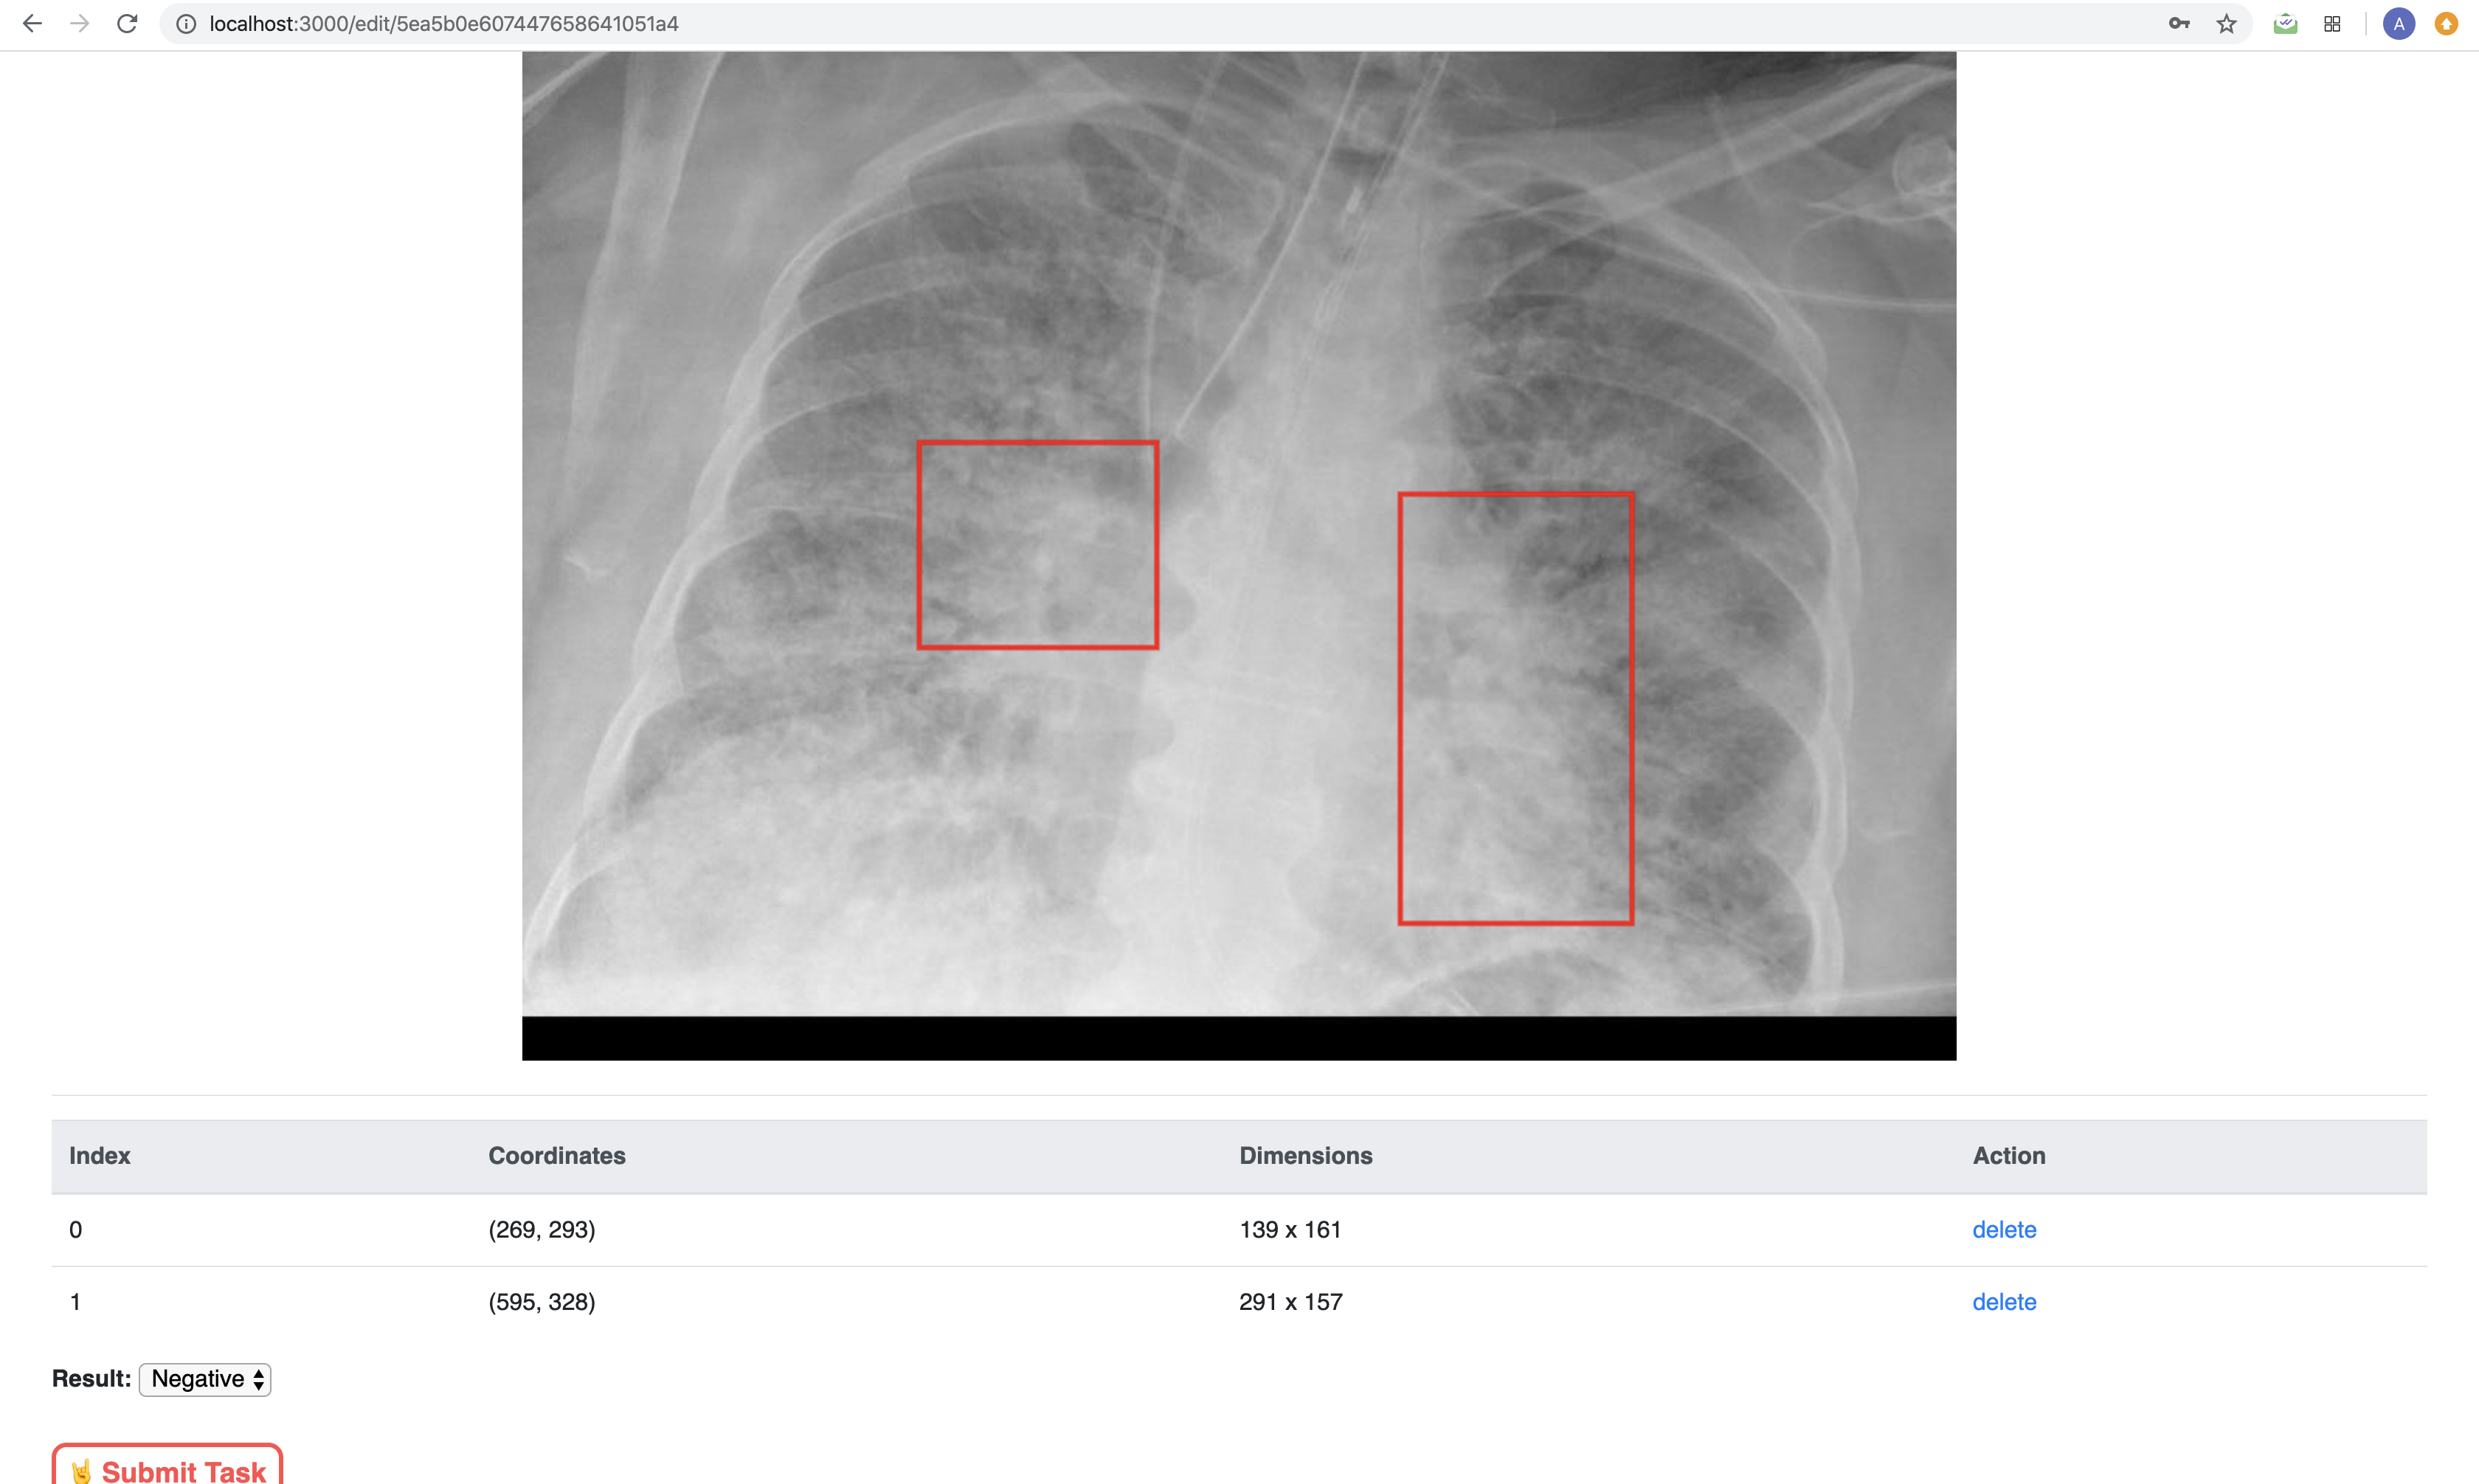

In addition to creating tasks, users can also label tasks. For images, they can draw bounding boxes and save these coordinates for the person who assigned the task. For PCR data, they can visualize the CSV data and view the coordinates of each point.

Our stack was React, MongoDB, Express, and Node.JS. All of our front end interactions involved React components where the user would interact with the page to send requests and data back to our MongoDB database. Images were stored as Base64 strings and CSV data was stored as JSON. When we graphed the RT-PCR data, we converted it from JSON to graphical format using the Recharts library. The bounding box implementation was done with Canvas tags in React. We also added an API for users to import existing email contacts from Outlook if they want to assign tasks specifically to someone in their own community with the Microsoft API. Our website is also HIPAA compliant because all data is de-identified.

It was difficult to find the appropriate implementation for the bounding boxes. Initially, we tried to store the boxes as

tags but found that to be too challenging so instead, we manipulated the Canvas tag to consistently update the image whenever events were detected by the user clicking and dragging on the screen.Accomplishments that I'm proud of